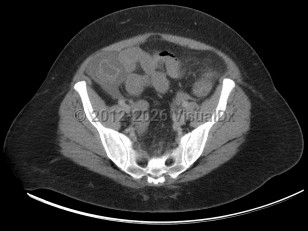

Small bowel obstruction

Intussusception